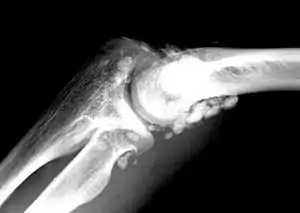

| X-ray of an elbow affected by synovial chondromatosis | |

In the early stages of the disease it is often confused with tendinitis and/or arthritis. Once it reaches transitional the loose bodies become apparent with X-ray in greater than 70% of cases, with MRI often showing where xray fails. In experienced hands, ultrasound is also useful for the diagnosis.[1]

In the disease, the thin flexible membrane of the synovium gradually forms blisters which calcify and enlarge. These nodules eventually break free and float around the joint space becoming larger – these add to the discomfort and stiffness of the joint.